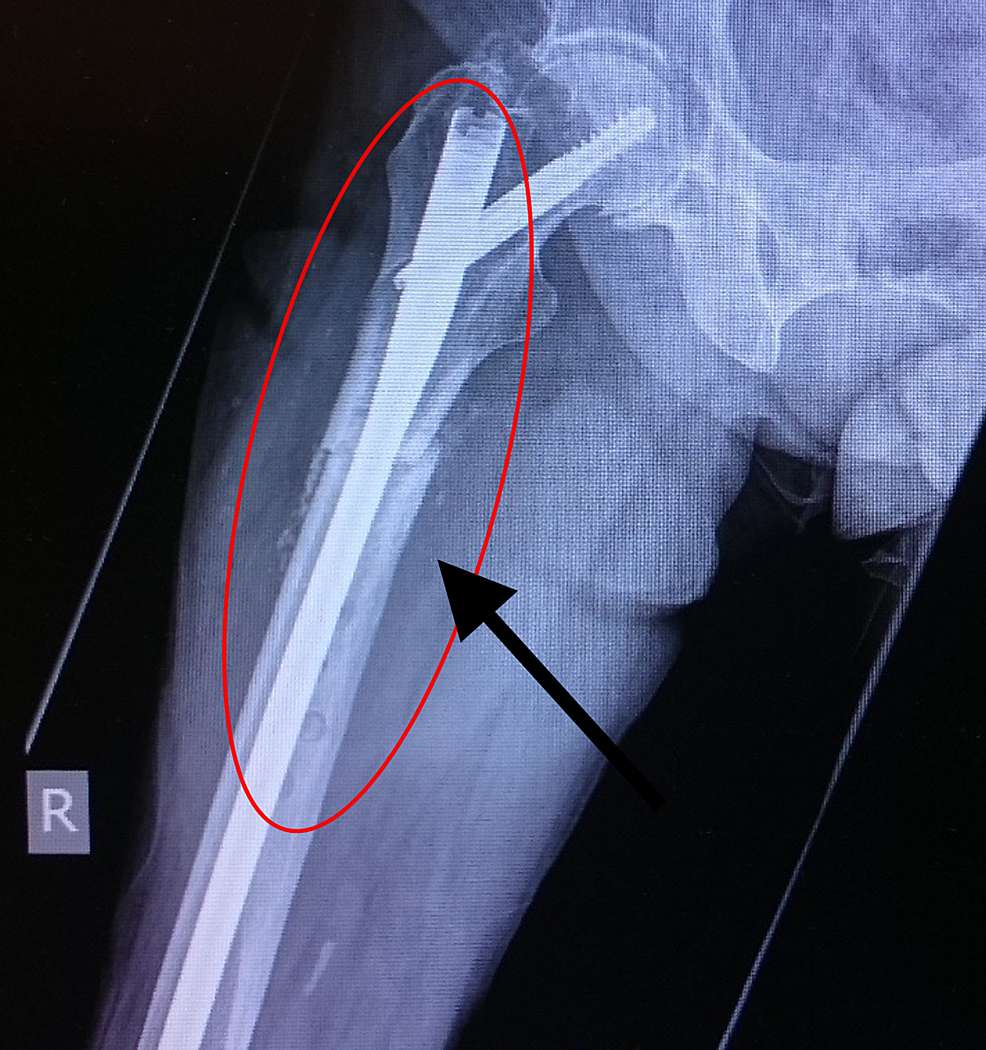

(a) Atypical left femur fracture sustained after a fall from standing

(a) Atypical left femur fracture sustained after a fall from standing Starting Bisphosphonate After Fracture early administration of bisphosphonates (bps) after surgery did not appear to delay fracture healing time either radiologically. upper gastrointestinal adverse effects, such as dyspepsia or reflux — these are common in the first month of treatment and often. osteoporosis is caused by the cumulative effect of bone resorption in excess of bone formation. eriksen et al.. Starting Bisphosphonate After Fracture.